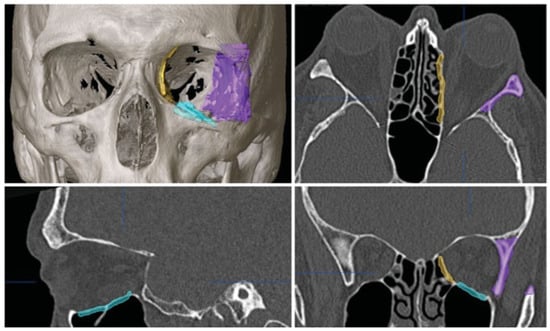

DICOM data from the CT study were imported into the planning software (iPlan CMF 3.0 BrainLab, Brainlab Inc., Westchester, IL) for preoperative planning. For each wall involved, the planned resection sites were indicated using different colors (Figure 2). A one-wall (orbital floor) decompression was planned on the right side and a three-wall decompression (lateral wall, floor, and medial wall) was planned for the left side.

Figure 2. Axial, coronal, and sagittal views with 3D reconstruction for patient 1, showing the preoperative plan. Areas of planned decompression are highlighted in color.